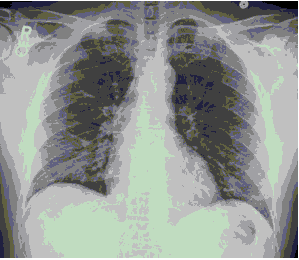

Стандартная РГ имеет низкую чувствительность в выявлении начальных изменений в первые дни заболевания и не может применяться для ранней диагностики. Информативность РГ повышается с увеличением длительности течения пневмонии. Рентгенография с использованием передвижных (палатных) аппаратов является основным методом лучевой диагностики патологии ОГК в ОРИТ. Применение передвижного (палатного) аппарата оправдано и для проведения обычных РГ исследований в рентгеновском кабинете. В стационарных условиях относительным преимуществом РГ в сравнении с КТ являются большая пропускная способность. Метод позволяет уверенно выявлять тяжелые формы пневмоний и отек легких различной природы, которые требуют госпитализации, в том числе направления в ОРИТ.

КТ имеет высокую чувствительность в выявлении изменений в легких, характерных для COVID-19. Применение КТ целесообразно для первичной оценки состояния ОГК у пациентов с тяжелыми прогрессирующими формами заболевания, а также для дифференциальной диагностики выявленных изменений и оценки динамики процесса. КТ позволяет выявить характерные изменения в легких у пациентов с COVID-19 еще до появления положительных лабораторных тестов на инфекцию с помощью МАНК. В то же время, КТ выявляет изменения легких у значительного числа пациентов с бессимптомной и легкой формами заболевания, которым не требуется госпитализация. Результаты КТ в этих случаях не влияют на тактику лечения и прогноз заболевания при наличии лабораторного подтверждения COVID-19. Поэтому массовое применение КТ для скрининга асимптомных и легких форм болезни не рекомендуется. При первичном обращении пациента с подозрением на COVID-19 рекомендуется назначать КТ только при наличии клинических и инструментальных признаков дыхательной недостаточности (SpO2 < 95%, ЧДД > 22).